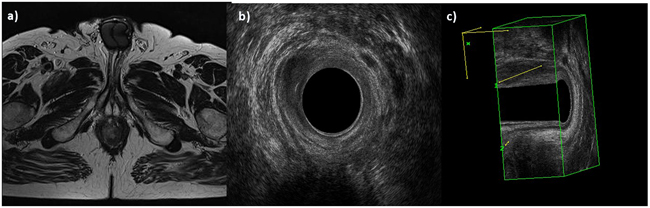

All lesions were hypoecoic on EAUS.

The lesions showed hyperintense signal on T2-W (Figure 2) and hypointense signal on T1-W. The diffusion was restricted from b0 s/mm2 to b800 s/mm2, with hyperintense signal on b800 s/mm2, hypointense signal on ADC map and the median ADC value was of 830x10-3 mm2/s (range, 760-904x10-3 mm2/s). All lesions showed a TIC type 3, with rapid initial and sustained late enhancement. In Table 2 we have summarized the aspects of the lesions on MR study.

Figure 2: Man 54y, anal cancer. In a. TSE T2-W in axial plane, the lesion infiltrates only internal sphincter, as showed also by 2 D b. and 3D c. EAUS.